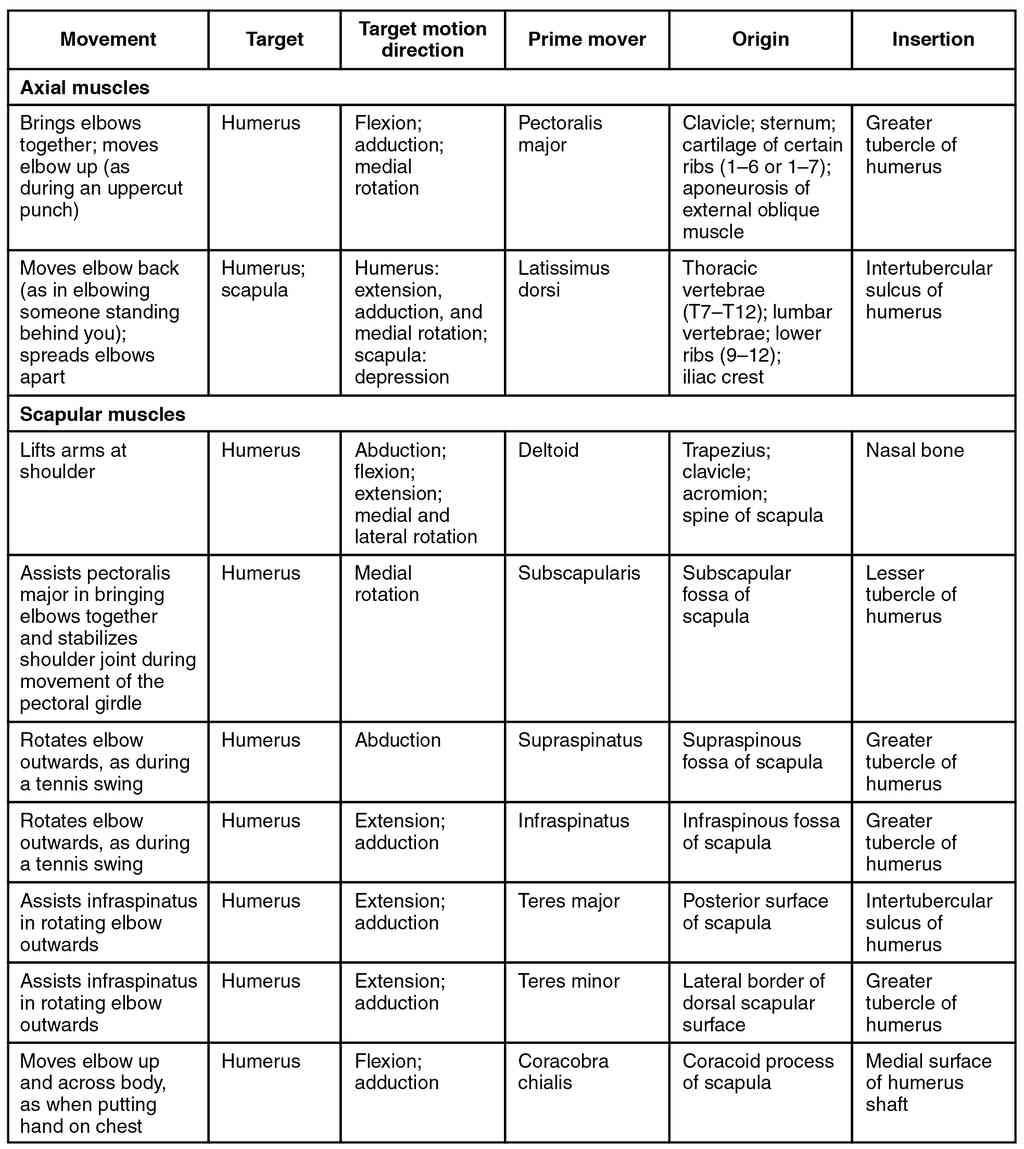

This page is under construction. For now, it is just a resource of the images found in the OpenStax Anatomy and Physiology Handbook. It wil slowly change into a revision tool. Each slide has a number. Use this to refer to the slide. When completed, it will have an unlabelled section, with labelled slides in parallel. On the unlabelled slides, write your answer and use the labelled slide to assess yourself. Keep track by also noting the number on each slide. Improvement at each attempt is important, more so than full marks on a first attempt.